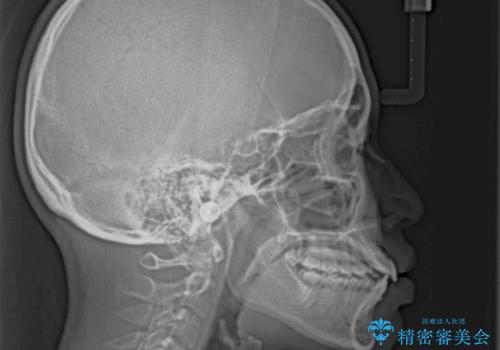

上下ともに歯列が前方に突出していたため、上下左右の第一小臼歯4本を抜去し、ワイヤー装置による矯正治療を行うこととしました。

上下左右4本抜歯する場合には、通常2年から2年半ほどの期間を要しますが、舌のトレーニングをしっかりと行っていただいたことで、1年9ヶ月で終了することができました。